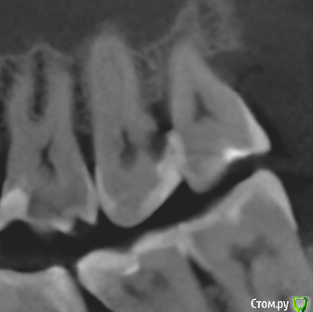

apex007 Опубликовано 26 января, 2021 Поделиться Опубликовано 26 января, 2021 Добрый день! 27 и 28 зубы немного развернуты в сторону щеки . В 27 серьезные разрушения со стороны 28, на уровне десны и под десну . Между 27 и 28 глубокий карман, видимо, из-за попадания остатков пищи в карман и возник кариес 27. Сейчас 27 вскрыт, врач предлагает удалить 28, чтобы можно было немного оттеснить десну и восстановить дистальную стенку 27. При этом 27 пришлось депульпировать, сейчас каналы еще не закрыты. Правильно понимаю, что удаление 28 приведет к ускорению рецессии кости и ухудшению прогноза для 27? Следует ли удалять 28 сейчас или восстановить 27 как получится и посмотреть на результаты эндодонтии через год (в 27 сложные каналы ), а карман промывать ирригатором? Фото по состоянию до начала лечения. Ссылка на комментарий